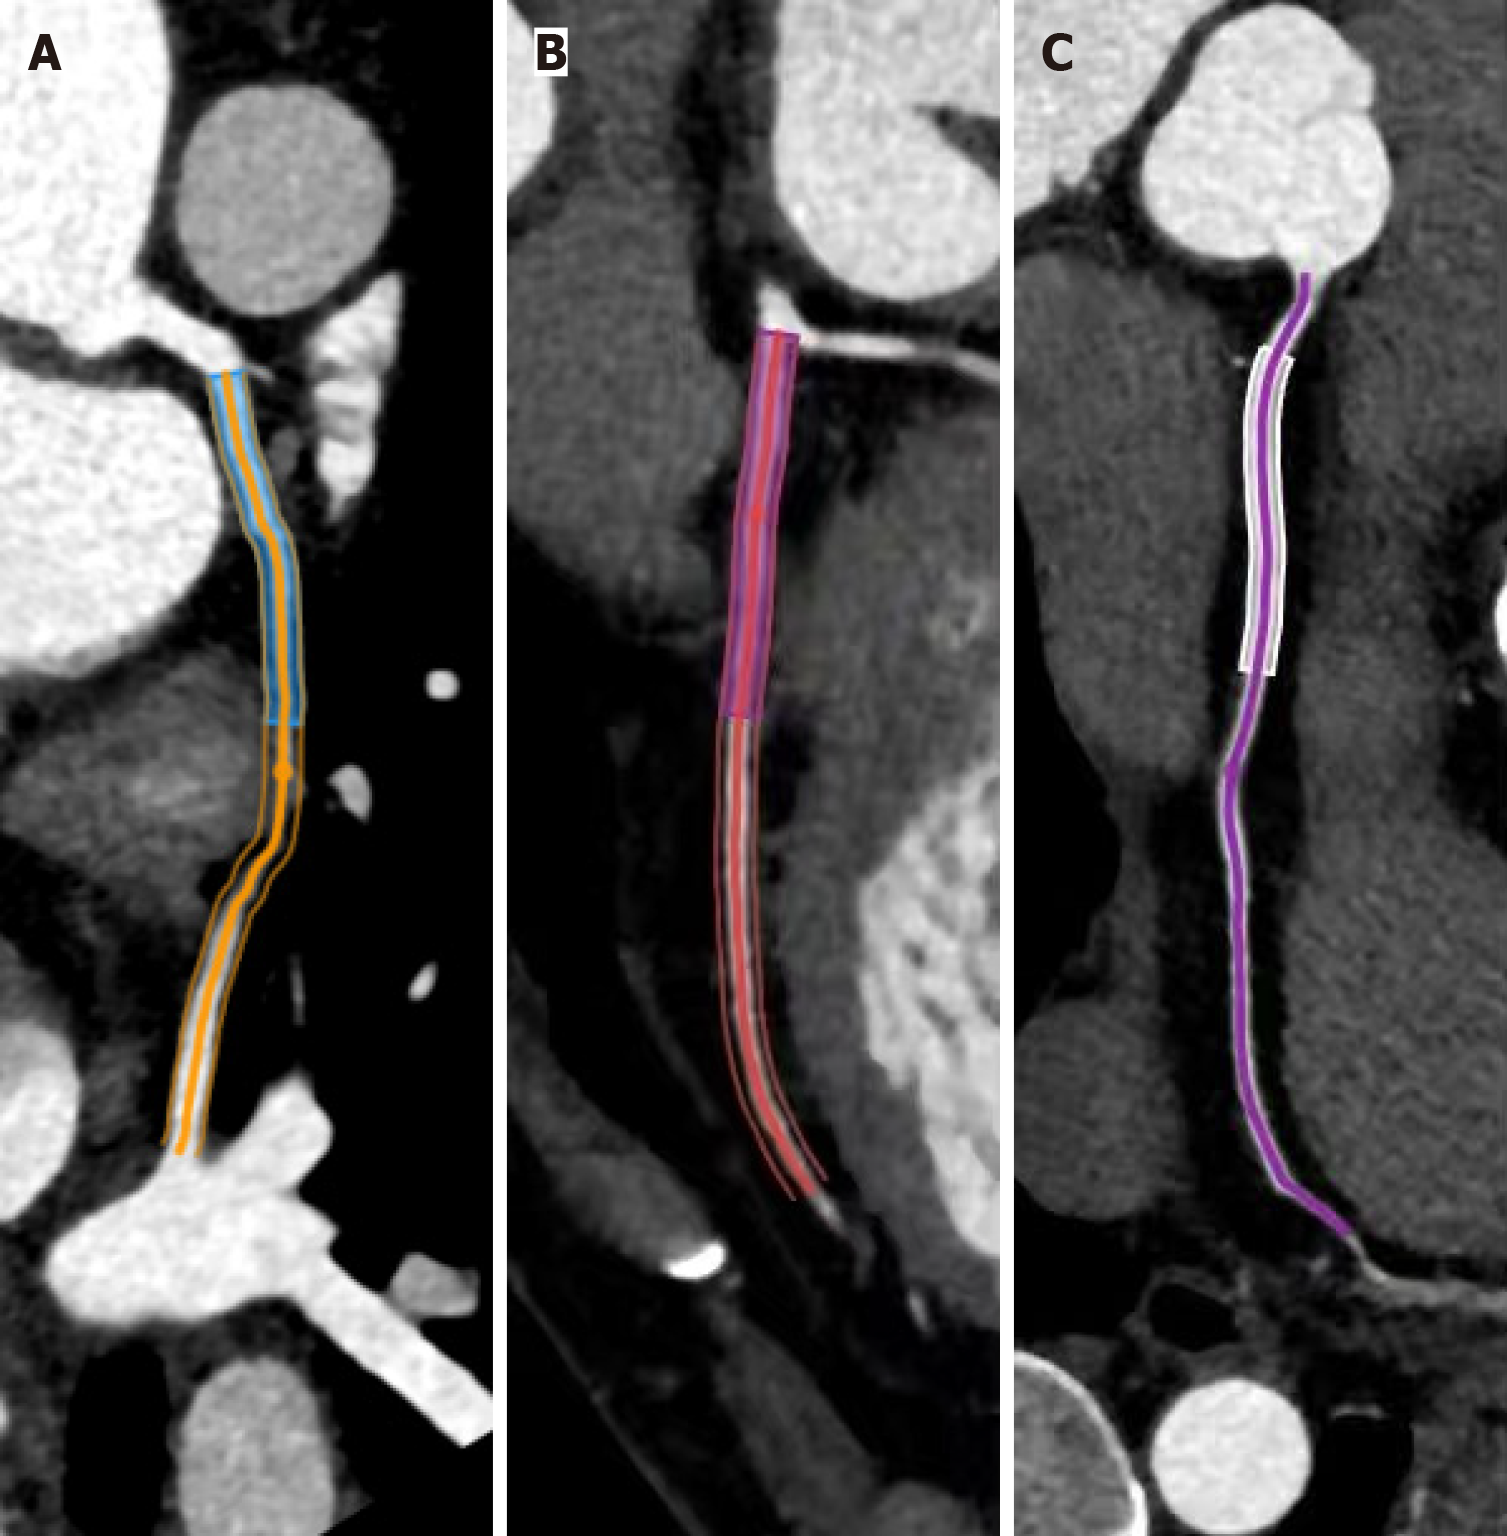

Figure 1 The methodology of the pericoronary adipose tissue analysis.

A: Left anterior descending artery; B: Left circumflex artery proximal 40-mm segments; C: Right coronary artery proximal 10-50 mm segment. Pericoronary adipose tissue attenuation was quantified within the adipose voxels (-190 HU to -30 HU), extending radially from the vessel wall at distances equivalent to the coronary artery diameters.